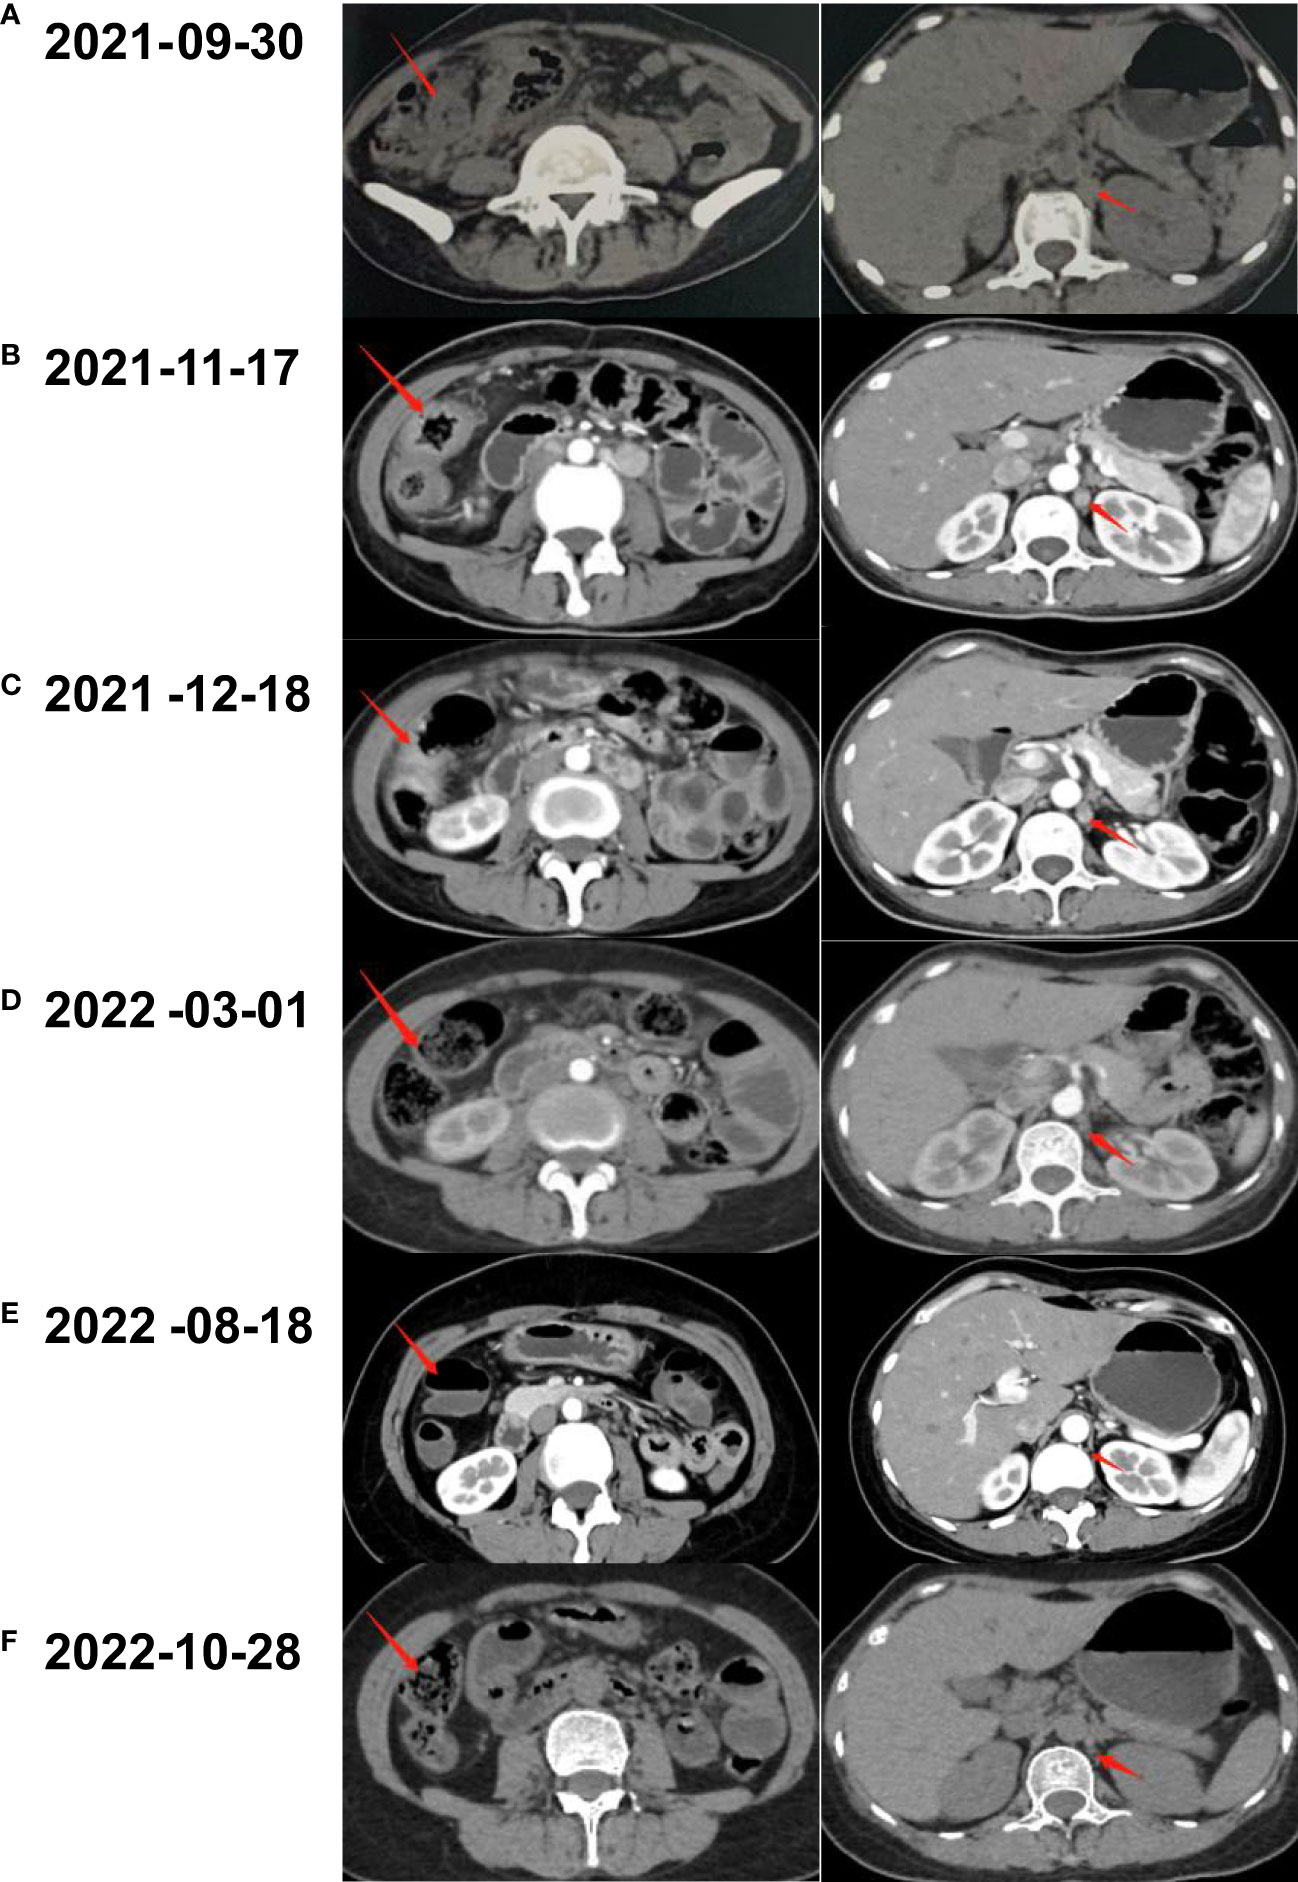

Coloscopy was performed, and pathological analysis of the tumor revealed adenocarcinoma (Figures 1C, D). Immunohistochemistry showed positivity for MLH1, MSH2, and MSH6 and negativity for PMS2. Next-generation sequencing confirmed that the tumor was MSH-H. However, the patient refused immunotherapy. Thus, a first cycle of chemotherapy consisting of mFOLFOX6 plus bevacizumab was administered on 1 October 2021. After three cycles, an abdominal CT scan showed an impressive reduction in tumor size in the right colon, while the retroperitoneal lesion remained stable. A chest CT revealed interstitial pneumonia (Figure 2), but the patient did not experience dyspnea. A multidisciplinary team (MDT) discussion, including surgical staff, was organized to formulate further treatment plans. Specialists recommended pembrolizumab, nivolumab, or nivolumab in combination with ipilimumab—all approved therapies for patients with metastatic MSI-H/dMMR colon cancer regardless of their eligibility for intensive therapy. Since the patient could not afford the expenses of the recommended courses of treatment, envafolimab was suggested instead. With patient and treatment teams reaching an agreement, the patient was started on envafolimab (150 mg, administered subcutaneously, once weekly) on 21 September 2021. Interstitial pneumonia did not worsen over the course of treatment, as evidenced by chest CTs. One month later, the patient experienced pain in her extremities with elevated creatine kinase (CK) and creatine kinase isoenzyme MB (CK-MB) levels. No significant laboratory findings involving cardiac troponins or N-terminal pro-brain natriuretic peptide were observed. We consulted cardiologists in our hospital. who excluded the possibility of ICI-related myocarditis but suspected myositis. However, she refused a proposal of muscle biopsy. According to the Management of Immune Checkpoint Inhibitor-Related Toxicity section of the Guidelines of the Chinese Society of Clinical Oncology, the symptom is classified in Grade 1, for which dose reduction or discontinuation are not considered. Therefore, nonsteroidal anti-inflammatory drugs (NSAIDs) and low-dose methylprednisolone (12 mg daily) were administered, and immunotherapy was continued. Decreased CK and CK-MB were observed three days after management (Figure 3). On 1 March 2022, a CT scan showed a decrease in volume, prompting a second MDT to suggest the patient continue treatment. A greater reduction in lesion size was observed during a follow-up CT scan in May 2022. Moreover, envafolimab with methylprednisolone (4 mg, daily) was well tolerated. Thirty-six cycles later, the lesion in the right colon disappeared on an abdominal CT scan performed on 18 August 2022 (Figure 4). Post-treatment colonoscopy revealed no neoplasm, and immunohistochemistry revealed chronic mucositis (Figures 1E, F). PET/CT also showed that the patient achieved CR efficacy (Figure 1B). Given the safety of envafolimab, the patient was started on 400 mg of envafolimab every 3 weeks without additional adverse events. CK and CK-MB levels remained low.

Figure 2 Abdominal CT scanning of the patient. (A) A neoplasm located in the right colon and thickened nodule in the retroperitoneal were shown by CT before treatment. (B) After three cycles of the combination of mFOLFOX6 and bevacizumab, CT demonstrated shrunken tumors in abdomen. (C) The lesion of colon and nodular did not continue to regress after another two cycles of chemotherapy plus targeted therapy. (D) CT scan revealed that the lesions came to gradual diminishment after eight cycles of envafolimab. (E) Thirty-six cycles of envafolimab later, the lesion in the right colon completely disappeared. (F) The patient kept clinical complete response with the use of envafolimab 400mg every 3 weeks.